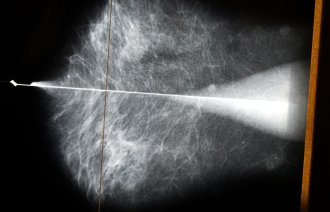

Enhertu som behandling mot brystkreft har i studier vist doblet progresjonsfri overlevelse sammenlignet med standardbehandling, og forbedret totaloverlevelse på over et halvt år, og legemiddelet ble i fjor innført til pasienter med aggressiv brystkreft.

Nå har Beslutningsforum åpnet for at det også kan brukes som behandling til pasienter med inoperabel eller metastaserende HER2-lav brystkreft fra 1. november, anslagsvis 250 hvert år.

Inoperabel eller metastatisk brystkreft vil si når kreftsvulsten ikke kan fjernes kirurgisk eller har spredd seg til andre steder i kroppen. Norge blir først ute med dette bruksområdet av land vi vanligvis sammenligner oss med – som Danmark, Sverige og England.